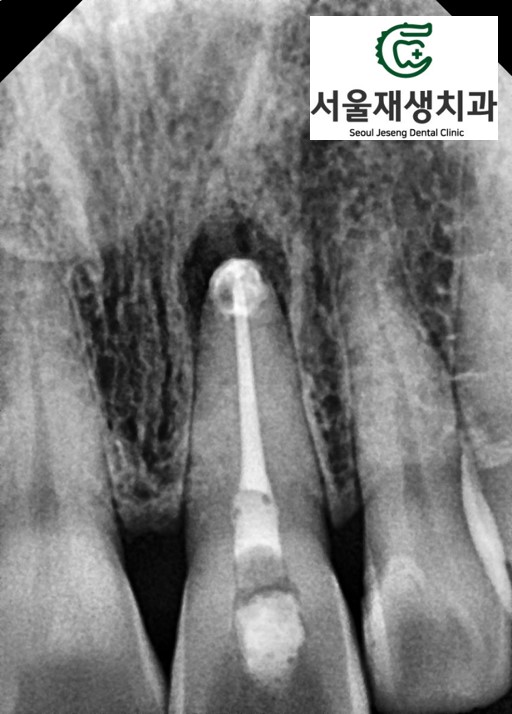

신경치료가 마무리되었습니다.

신경이 들어있던 빈 공간을

깨끗히 청소하고,

빈틈없이 밀봉합니다.

신경치료를 마무리하는 날,

치아 뒷면에 뚫린 구멍을 통해

미백 약제를 넣어줍니다.

치아 뒷면을 통해

모든 치료가 진행되기 때문에,

앞에서 보기에는

치아 색상이 밝아지는 것 외엔

달라지는 것이 없습니다^^